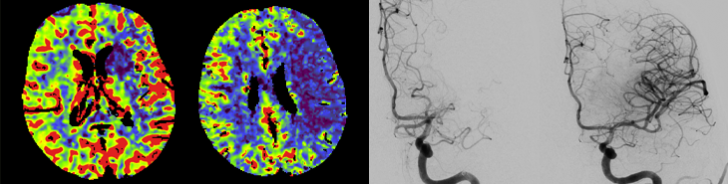

Neuroradiology is your contact partner for diagnostics and minimally invasive therapy of diseases and changes of the nervous system, i.e. of the brain and spinal cord, peripheral nerves and the immediate adjacent structures (e.g. the spine).

Diagnostically and therapeutically, the most modern methods and equipment are available for our patients. In addition to diagnostic neuroradiology, our clinic is characterized by a high level of expertise in minimally invasive neuroradiological therapy, both in the emergency treatment of strokes and in the elective treatment of aneurysms, vascular stenoses and vascular malformations.